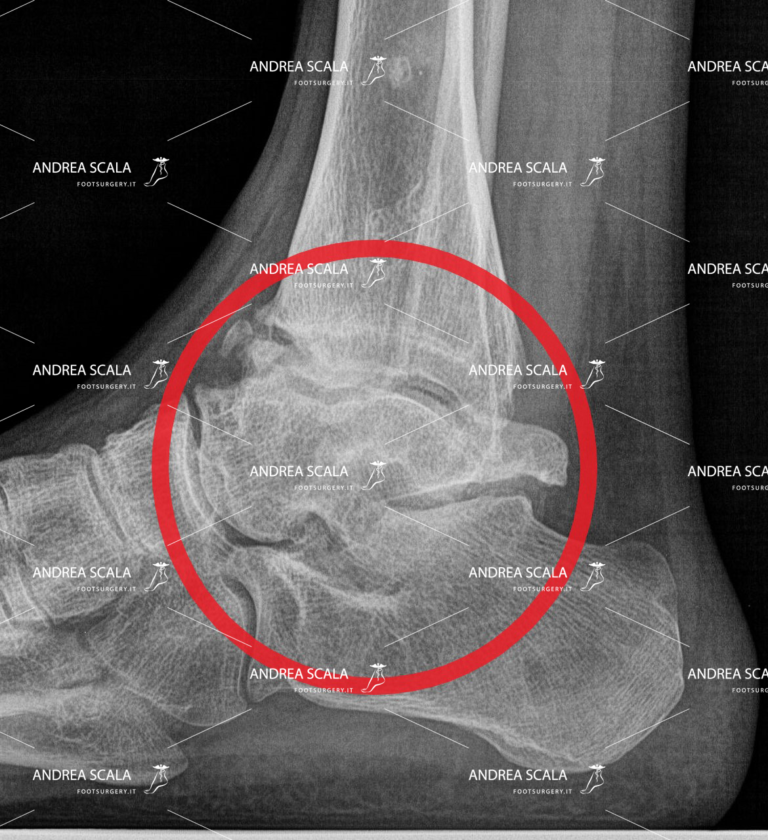

Come si diagnostica l’artrosi alla caviglia?

Con un’analisi attenta dei sintomi, alla quale va immediatamente accompagnata una radiografia che ha lo scopo di far emergere le evidenze più marcate legate all’artrosi, ovvero una rima articolare assottigliata, il rimodellamento dell’osso che si trova al di sotto della cartilagine articolare, la presenza di cisti ossee e piccoli speroni ossei.